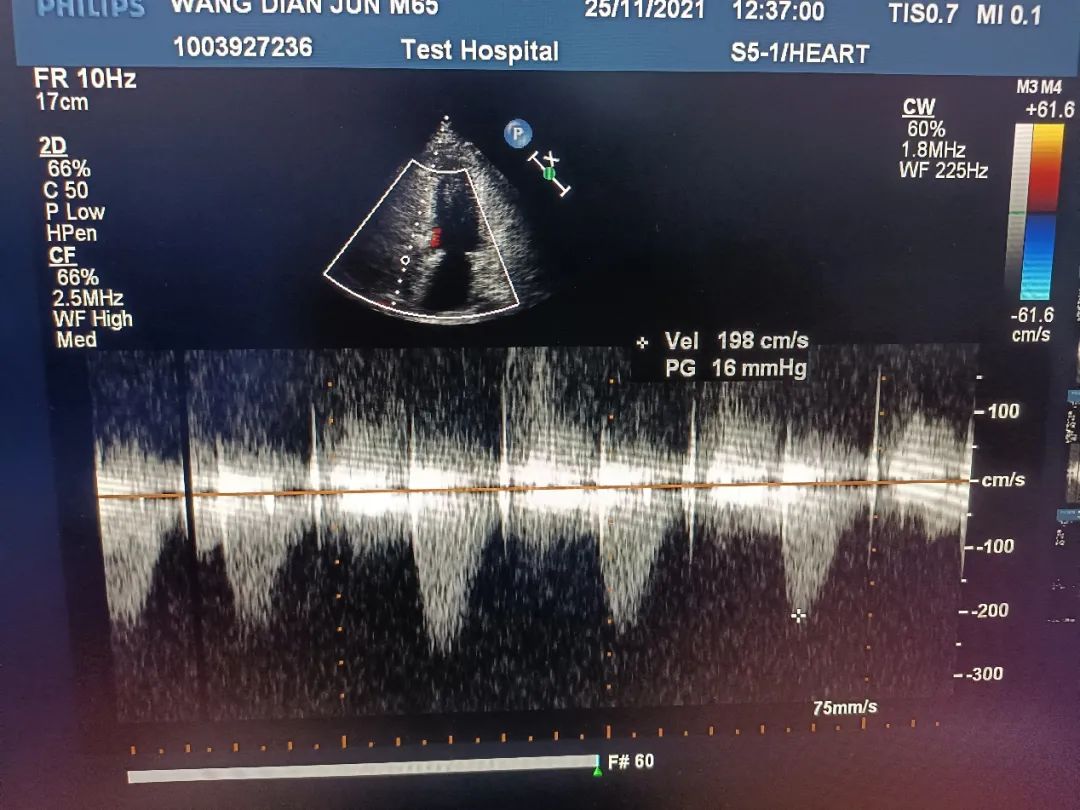

术中超声

超声结果示:微量瓣周漏,主动脉瓣口峰值流速为1.98 m/s,峰值跨瓣压差为 16 mmHg